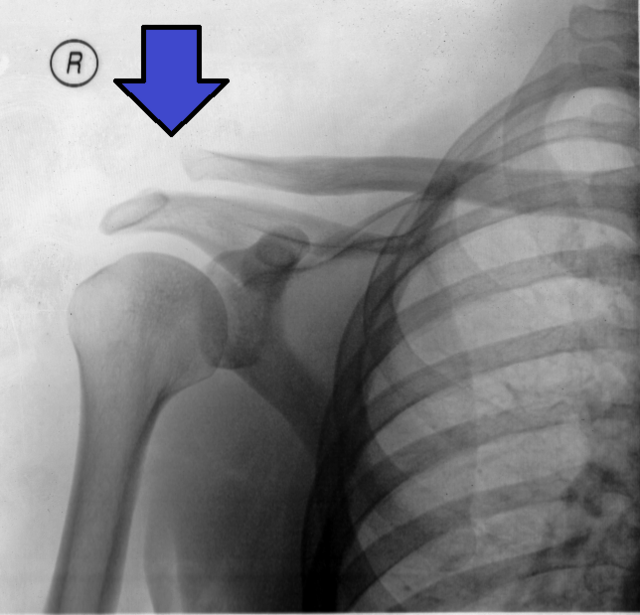

Depresjon av acromion kan føre til en synlig heving av clavicula, noe som gir en karakteristisk deformitet.

Rockwood-graderingssystemet

Grad 1: Forstuing av AC-ligamentet uten synlig separasjon.

Grad 2: Delvis ruptur av AC-ligamentet, liten separasjon.

Grad 3: Fullstendig ruptur av AC- og CC-ligamentene, med markant separasjon.

Grad 4: Clavicula dislokeres posteriort inn i trapezius.

Grad 5: Større dislokasjon med betydelig deformitet og vevsskade.

Grad 6: Clavicula dislokeres inferiort, under coracoidprosessen.

Grad III:

Beskrivelse:

Fullstendig ruptur av både AC- og CC-ligamentene, uten betydelig skade på delto-trapezial fascien. Beskrevet som dislokasjon.

Observasjon/Testing:

Deformitet med clavicula som ser forhøyet ut (deprimert acromion). Clavicula er ustabil i både vertikal og horisontal retning.